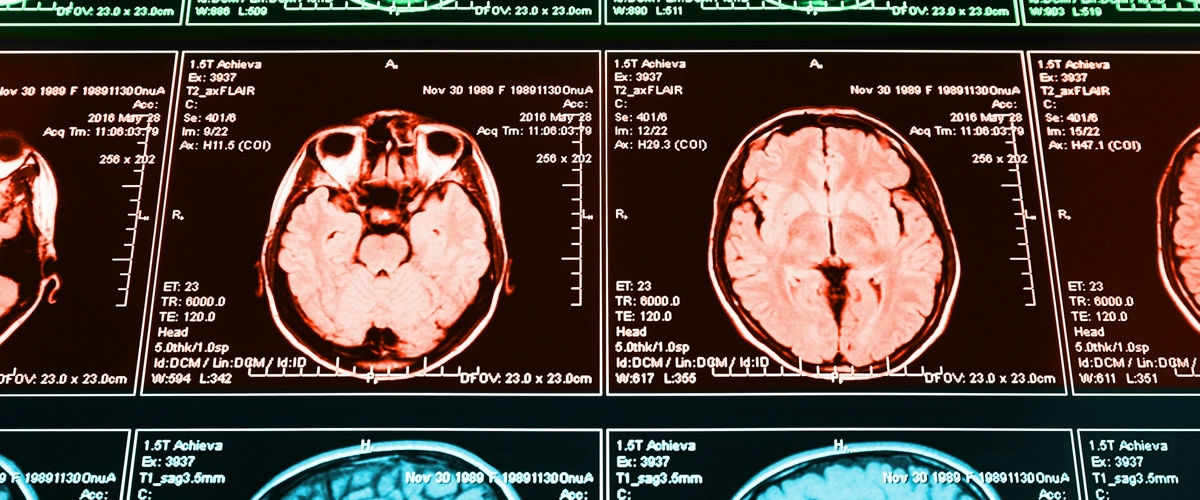

Ученые провели масштабную работу: они проанализировали поведение более тысячи здоровых людей, сопоставив их психологические тесты с данными функциональной и диффузионной МРТ. В расчет брали всё — возраст, эмоциональное состояние, даже уровень IQ. И знаете, что обнаружилось?

Агрессия, как выяснилось, рождается на «перекрестке» двух крупнейших магистралей мозга: сети пассивного режима (когда мы витаем в облаках и ведем внутренний диалог) и сети активного режима (когда мы сосредоточенно работаем с внешним миром).

В норме эти сети должны работать по очереди, как качели. Но представьте, что они включаются одновременно и начинают мешать друг другу. Внешние раздражители не дают вам спокойно подумать, а навязчивый внутренний голос не замолкает, даже когда нужно сконцентрироваться на задаче. Звучит как рецепт для нервного срыва, не правда ли? Именно такая чрезмерная связность, как показало исследование, коррелирует со вспышками гнева и даже физической агрессией.